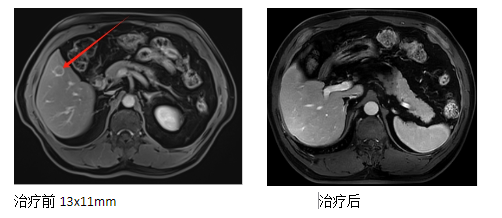

2. Medical History: The patient underwent a physical examination at our hospital on December 31, 2021. Abdominal MRI revealed liver cirrhosis and a small hepatocellular carcinoma in segment S5 of the liver. On January 4, 2022, a liver biopsy was performed. Pathological results indicated hepatocellular carcinoma (liver mass biopsy tissue). Immunohistochemistry results showed: CD34 (+), CK19 (small bile ducts +), CK7 (small bile ducts +), Glypican-3 (+), Hepatocyte (+), and Ki-67 (positivity rate approximately 15%). Surgical treatment was recommended, but the patient and family refused due to the high surgical risks. Subsequently, the patient underwent carbon ion radiotherapy in our department in January 2022, with a dose of DT: PTV: 45 GyE/10 fractions, and an iTV boost of 15 GyE/10 fractions. Follow-up examinations showed complete disappearance of the lesion.

4. Treatment Outcome: